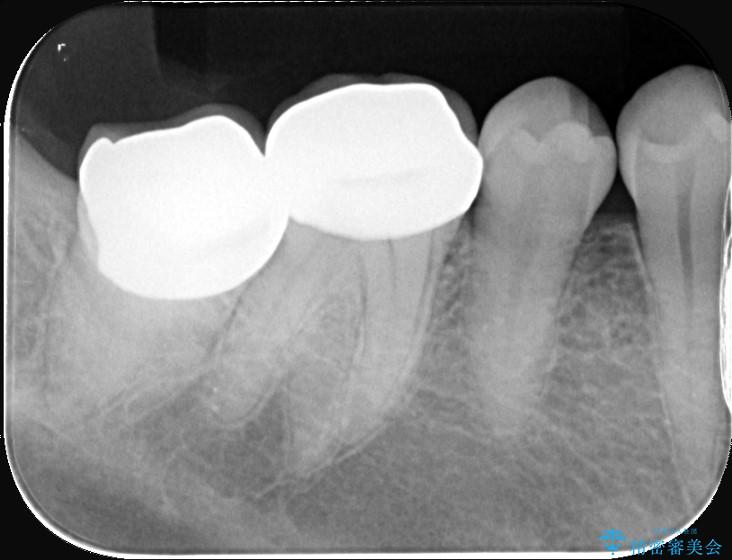

歯と歯の間に虫歯があった患者様です。

噛む面や外側にも過去の詰め物が入っている状態で、このように詰め物の範囲が大きいと治療後に歯が割れてしまうリスクが高くなります。

今回は歯の強度と将来的な破折リスクを考慮し、セラミッククラウンによる治療を行うこととしました。